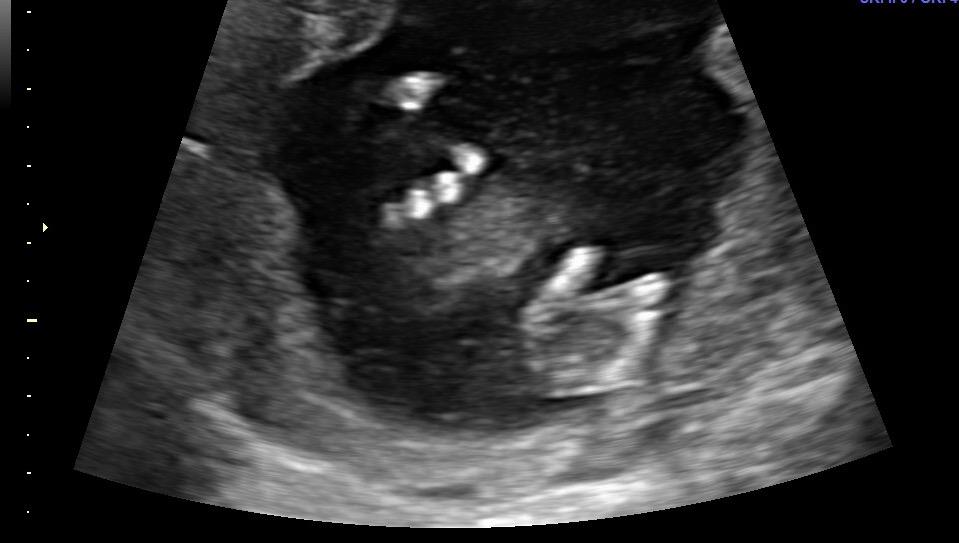

My baby giving the ultrasound tech a hard time, wouldn't keep their little toes out of their mouth☺️

Team Green